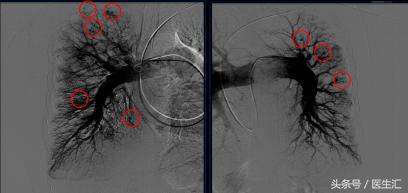

肺动脉造影+右心导管检查

造影所见:肺动脉主干及叶肺动脉明显增粗,双侧肺动脉分支未见明显扭曲,未见明显充盈缺损,可见弥漫性动静脉瘘,远端灌注良好